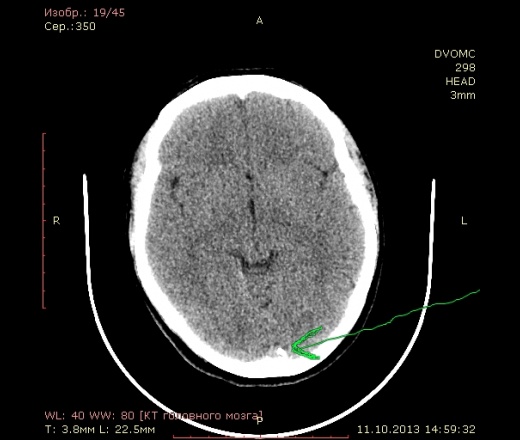

42 года. Слева в лобной доле кровоизлияние в 2011 году. Это понятно.

Есть другой вопрос нормальное ли обызвествление в затылочной доле?

А это не синус?

Может обызвествление твердой мозговой облочки.